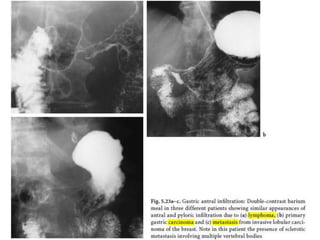

heterogeneous attenuation pattern. The size of

this lesion together with the lack of definition

of its margin suggest that this is frankly

malignant

Malignancy??

• 10 per cent are malignant.

• Unfortunately, the prediction of malignancy is difficult even by

histological criteria.